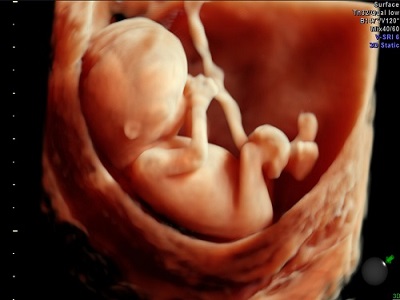

Imagen 3D y 4D

Ultrasonido de 3D y 4D

La principal diferencia entre ambos es que el 4D muestra imágenes en movimiento, mientras que el 3D las muestra estáticas.